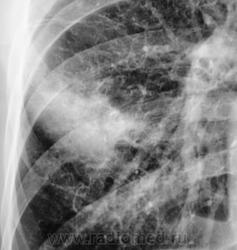

Контроль через неделю после проведения неспецифической противовоспалительной терапии.

1.pc170021.jpg2.pc170022.jpg3.pc170022a.jpg4.pc170023.jpg5.pc170024.jpg